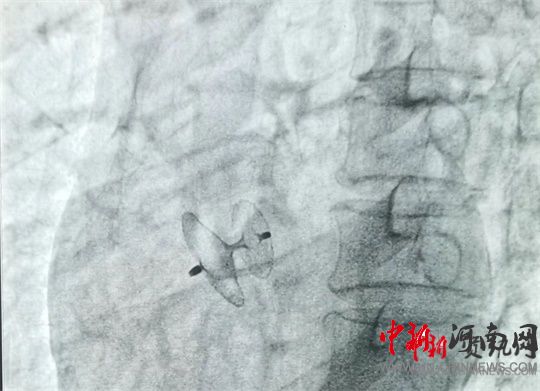

岳軍帶領團隊將封堵器通過股靜脈送至卵圓孔處,展開封堵傘,使其與卵圓孔完美契合,成功封堵住缺口。經(jīng)床旁彩超證實,無殘余分流,手術過程十分順利,全程僅用時60分鐘。術中及術后,患者均未出現(xiàn)不良反應,術后12小時即可下床活動。